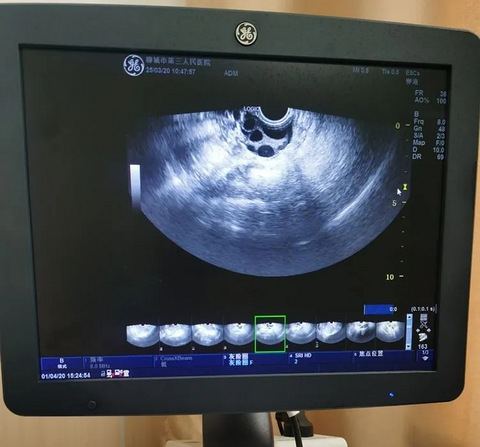

来自医生分享:门诊有一对年轻夫妻,30岁出头,说还没有怀孕的打算。但是想了解一下自己目前的生育能力,好为以后做好准备。现在的年轻人想法真是奇特!生育力检查,主要是这几项:第一、性激素六项和AMH。主要用于判断卵巢功能。第二、B超。看窦卵泡个数,以及排除子宫肌瘤、卵巢囊肿、生殖道畸形等影响怀孕的疾病。第三、男方精液常规检查。判断男方的精子质量。第四、男方精子DNA碎片率,也就是DFI。这个检查也很重